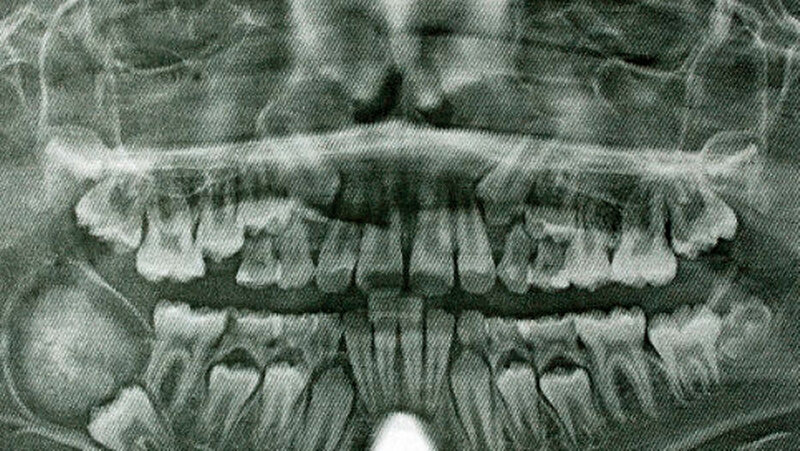

Zur Vorstellung brachte der Patient eine von seinem Hauszahnarzt angefertigte Panoramaschichtaufnahme mit, auf der sich der Zahn 47 retiniert und nach kaudal verlagert zeigte (Abbildung 1). Des Weiteren befand sich im Bereich des rechten Kieferwinkels eine ausgedehnte rundliche Verdichtung mit transluzentem Randbereich. Diese Raumforderung stand in direktem Kontakt zur Krone des retinierten und verlagerten Zahnes 47. Der Canalis mandibularis stellte sich nicht dar.